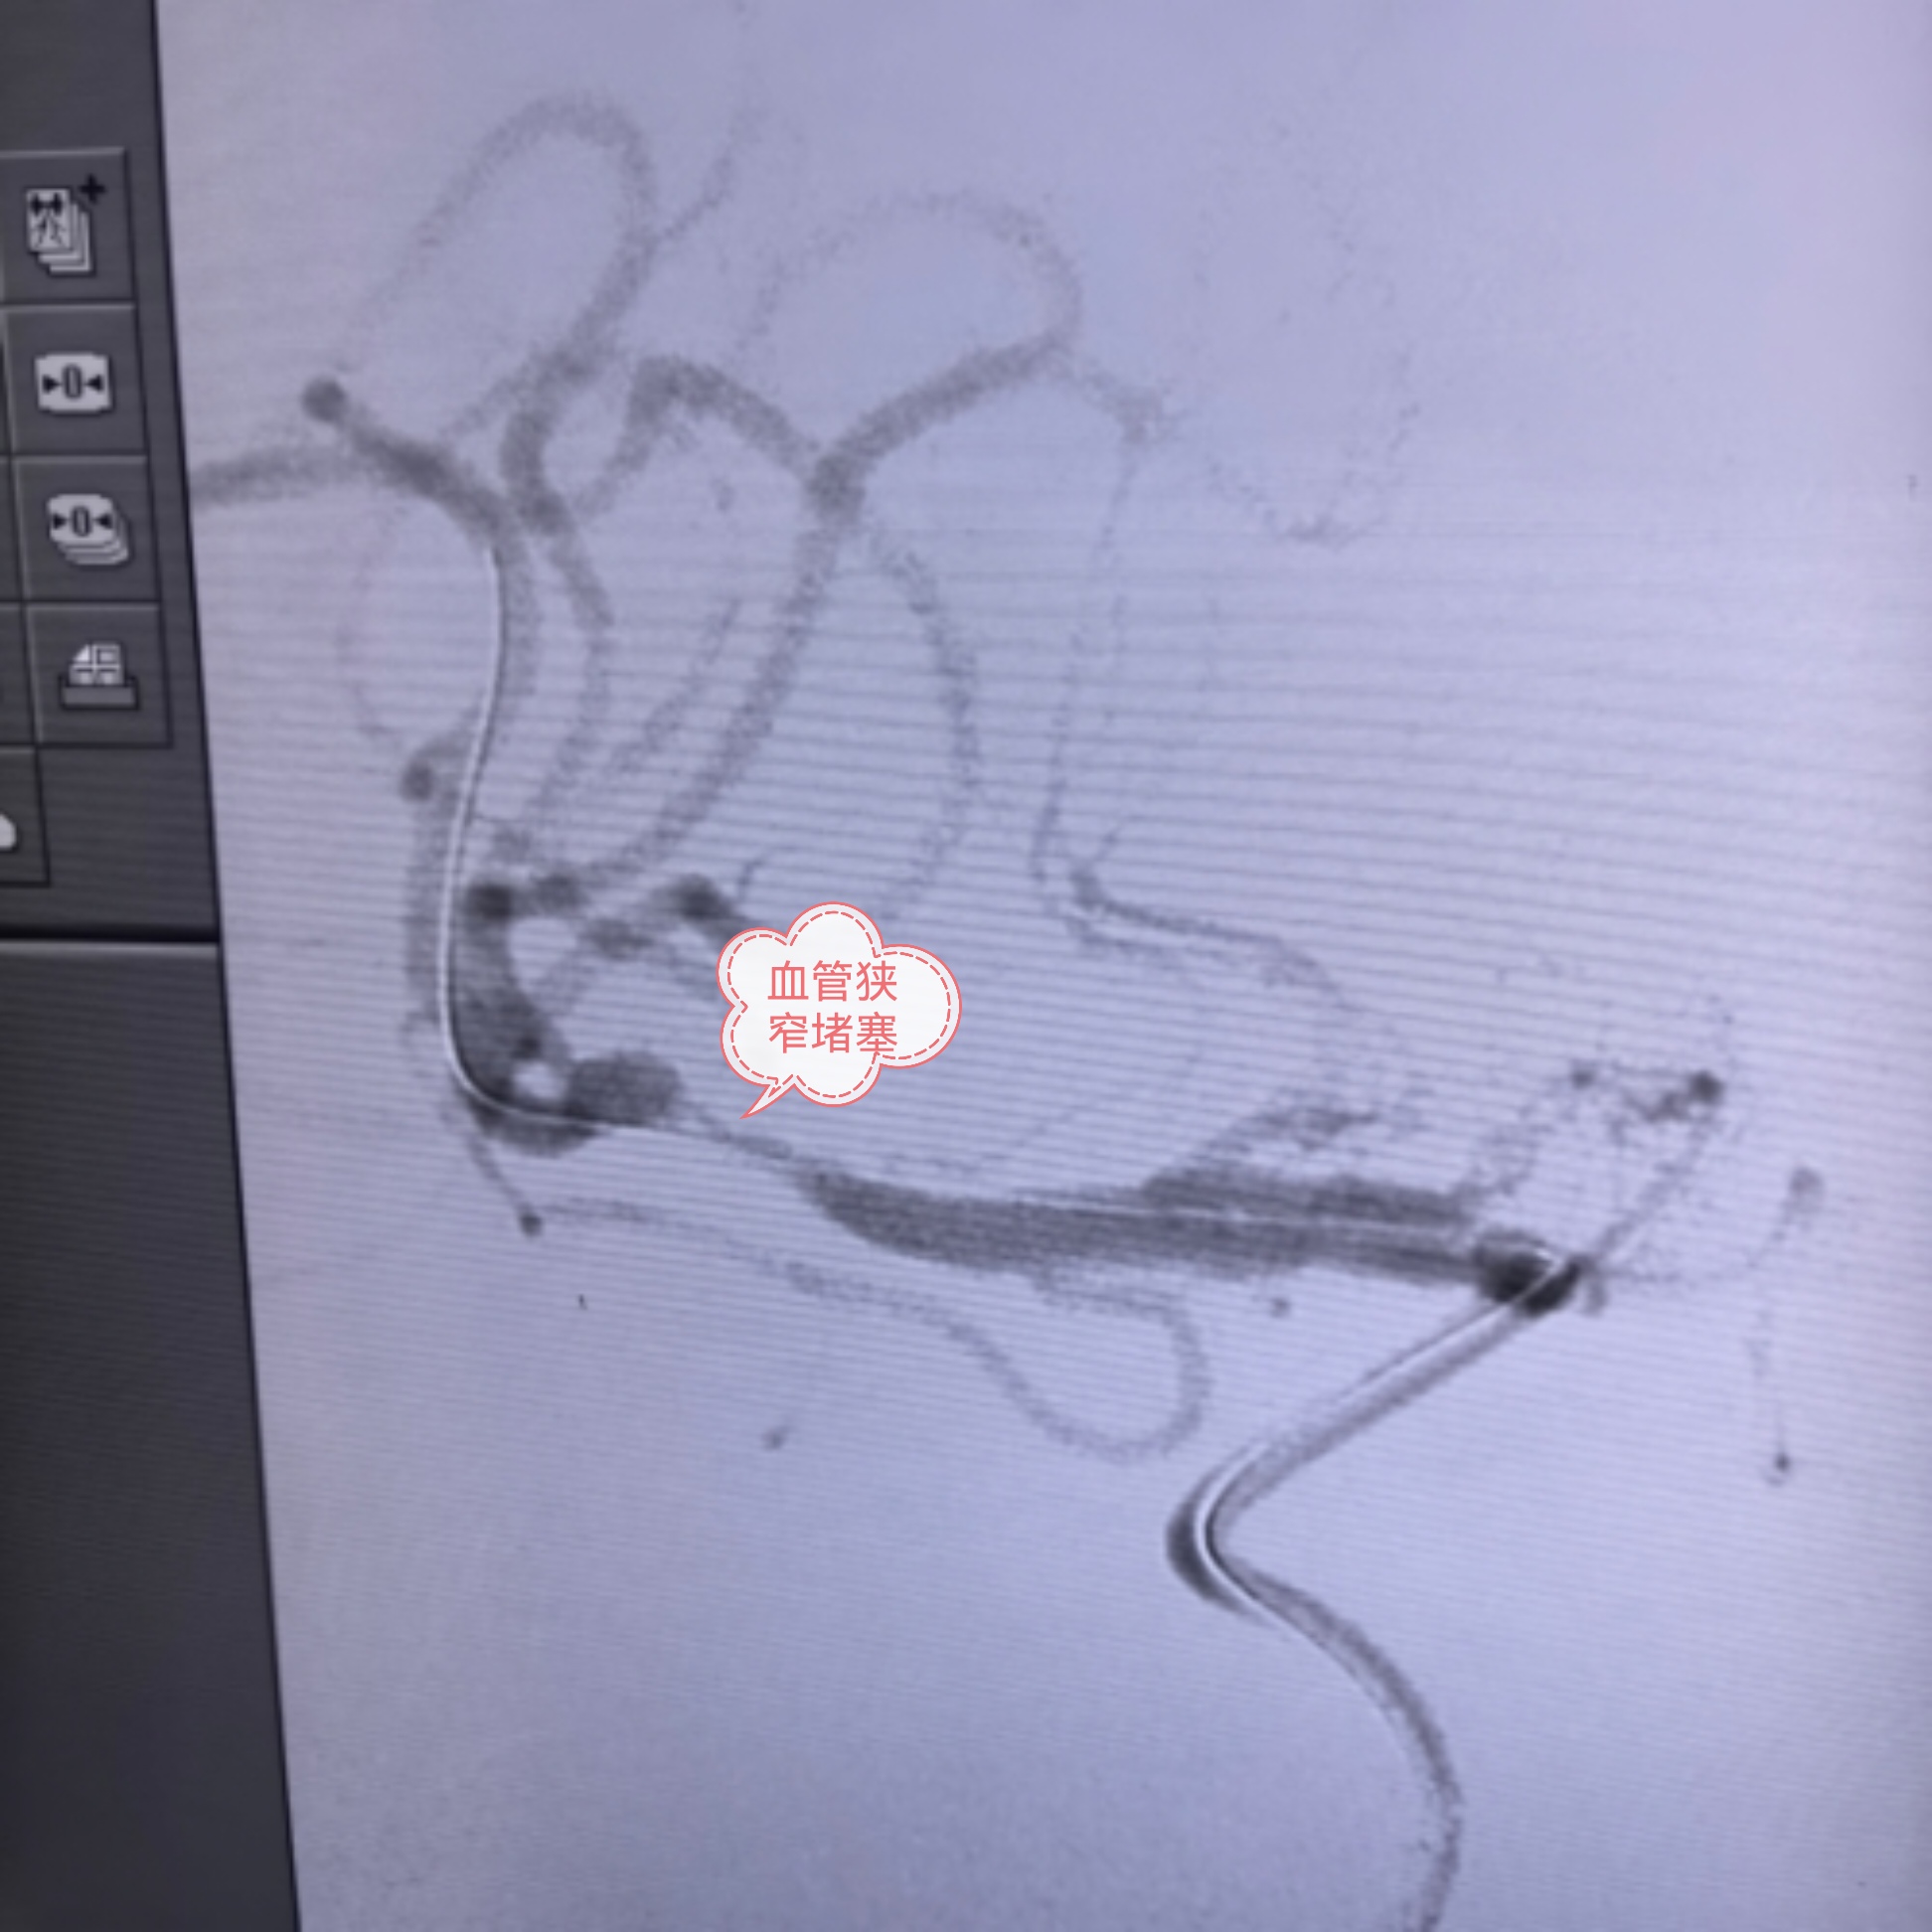

次日凌晨5:00,第四台急诊手术接力开展,患者为左侧大脑中动脉闭塞,且颈总动脉起始段极度扭曲,同时合并大脑中动脉原位狭窄,手术难度极大。团队迎难而上,顺利完成取栓手术并行颅内球囊扩张,成功打通生命通道。

大家常说,时间就是大脑。对于卒中患者而言,早一分钟开通血管,就多一分康复的希望。我们深知,多争取一秒,患者就少一分残疾,多一分回归家庭的可能。凭借成熟的卒中中心建设、规范的绿道流程,以及过硬的介入技术,三台取栓手术均获成功。患者术后血管再通,肢体功能迅速恢复,从昏迷瘫痪到恢复自如,真正实现了“入院重危,出院安康”。